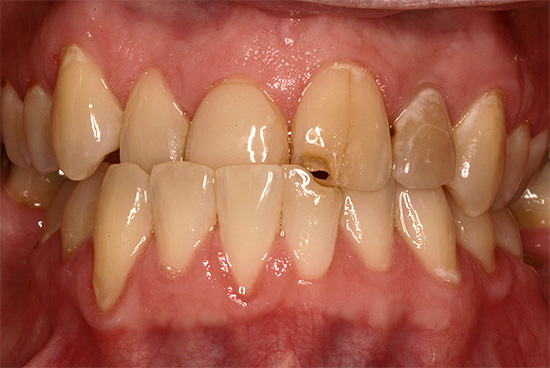

La fotografia sotto mostra un esempio di morso incrociato in un adulto:

Reclami frequenti da pazienti e genitori:

- la presenza di un difetto estetico con una notevole discrepanza tra dimensione e posizione delle mascelle;

- difficoltà a mangiare;

- violazione della pronuncia del suono;

- malattia gengivale dovuta a possibili lesioni durante la masticazione e la parola;

- problemi al tratto gastrointestinale.